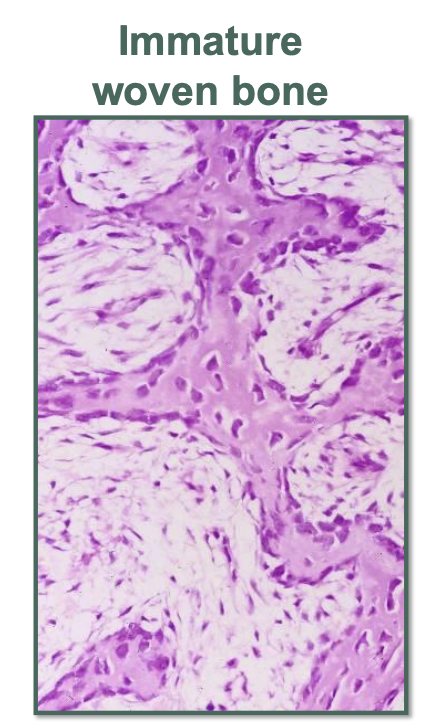

What is the histopathological presentation of fibrous dysplasia?

A

• fibrous replacement of bone

• cellular fibrous tissue

How well did you know this?